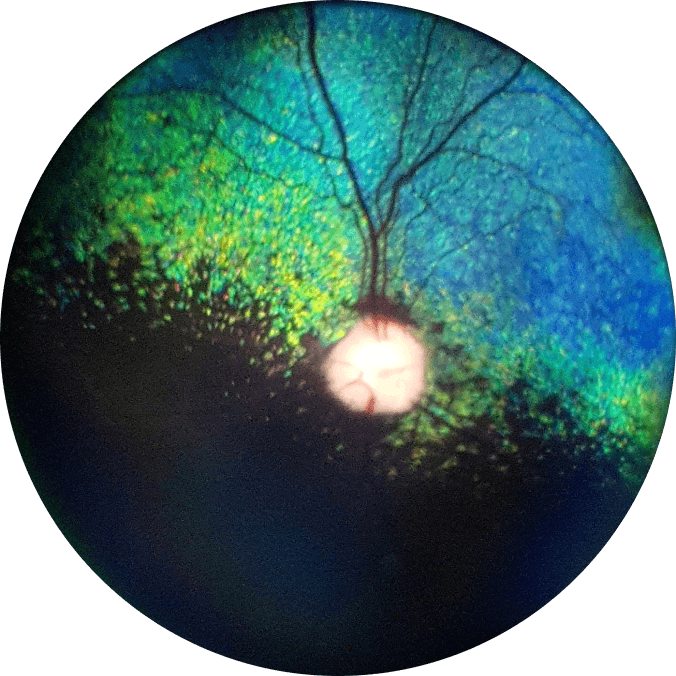

Bichon Frisé

undilated, 2y, OS